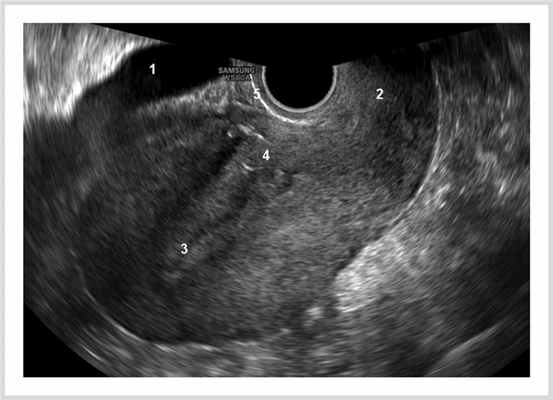

Нормальной картиной послеродовой матки считали инволюцию матки, соответствующую суткам послеродового периода: сомкнутую полость в виде линейного М-эха или расширение полости до 10 мм с однородным гиперэхогенным содержимым (рис. 1). Рис. 1. Нормальная эхограмма послеродовой матки. 1 — мочевой пузырь; 2 — шейка матки; 3 — нормальная полость матки; 4 — нормальный шов после кесарева сечения; 5 — неизмененная пузырно-маточная складка.